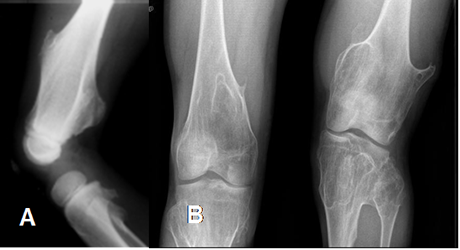

Fig 75. Osteocondroma.

A: Rx AP, B: Rx axial y C: TAC axial. Exostosis en el cuello femoral, que tiene continuidad con la medular del hueso, por osteocondroma.

Fig 78. Osteocondroma.

A: Rx lateral y B: Rx AP. Osteocondromatosis múltiple en diferentes pacientes .